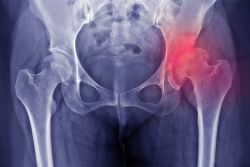

Thoái hoá khớp háng là bệnh lý do hậu quả của tuổi tác và mài mòn khớp. Thoái hoá khớp háng gây đau và biến đổi cấu trúc của khớp, dần dần dẫn đến tàn phế, ảnh hưởng đến chất lượng cuộc sống, là gánh nặng cho gia đình và xã hội. Thoái hoá khớp háng nếu được chẩn đoán và điều trị sớm có thể làm chậm phát triển của bệnh, giảm triệu chứng đau, giúp bệnh nhân vận động, trở lại cuộc sống hàng ngày.

- Hẹp khe khớp: dấu hiệu chứng tỏ mòn sụn khớp

- Mọc gai xương: phát triển ở tất cả các vị trí, ở cả chỏm xương đùi và xương chậu, chính điều này giải thích tại sao các động tác của khớp háng bị hạn chế

- Đặc xương dưới sụn: thấy ở vùng chịu lực tỳ lớn

- Khuyết xương: rất thường gặp, đôi khi có kích thước lớn